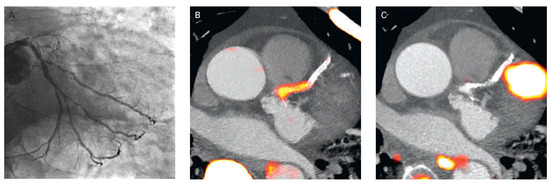

Contributions of Cardiac PET/CT to Better Assess the Cardiovascular Risk

by Ines Valenta, Alessandra Quercioli and Thomas H. Schindler

Cardiovasc. Med. 2015, 18(3), 83; https://doi.org/10.4414/cvm.2015.00303 (registering DOI) - 18 Mar 2015

Imaging of myocardial perfusion with SPECT, SPECT/CT and PET/CT is widely used for the detection of flow-limiting epicardial lesions and risk stratification of patients with suspected or known CAD. While regional reductions in radiotracer uptake during stress as compared to rest identify flow-limiting [...] Read more.

Imaging of myocardial perfusion with SPECT, SPECT/CT and PET/CT is widely used for the detection of flow-limiting epicardial lesions and risk stratification of patients with suspected or known CAD. While regional reductions in radiotracer uptake during stress as compared to rest identify flow-limiting effects of the most advanced focal epicardial lesions, the haemodynamic significance of less severe obstructive CAD lesions in multivessel disease or the presence of subclinical and nonobstructive CAD may be missed. The concurrent ability of PET/CT to determine regional myocardial blood flow (MBF) in ml/g/min at rest and during pharmacologically induced hyperaemic flows allows the calculation of the myocardial flow reserve (MFR). Adding the hyperaemic MBF and MFR to the conventional visual analysis of myocardial perfusion (1.) signifies reductions in coronary vasodilator capacity, as functional precursor of the CAD process, and determines its response to preventive medical intervention, (2.) provides important prognostic information in subclinical – and clinically manifest CAD, as well as in cardiomyopathy, (3.) improves the identification and characterisation of the extent and severity of CAD burden; and (4.) contributes to denote the flow-limiting effect of single lesions in multivessel CAD. The diagnostic scope of PET/CT, however, extends beyond myocardial flow to the identification of hibernating stunning myocardium in ischaemic cardiomyopathy, cardiac sarcoid involvement, and inflammatory coronary plaque burden. It is anticipated that with the advent of PET/MRI (magnetic resonance imaging) further advances and refinement in the comprehensive assessment of cardiovascular pathology will ensue. Full article